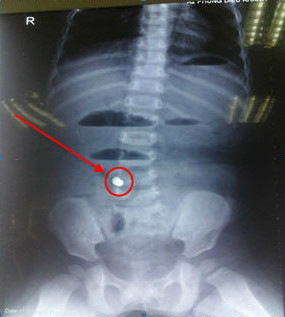

| Trẻ vô tình nuốt phải 4 hạt kim loại dính vào nhau, gây nên tắc ruột. Ảnh: Bệnh viện cung cấp. |

Qua thăm khám, chụp X-quang, siêu âm bụng, các bác sĩ phát hiện có hình ảnh của dị vật trong bụng trẻ. Ngay lập tức bé được mổ nội soi cấp cứu, cắt đoạn ruột bị tổn thương có chứa dị vật khoảng 5cm (có 4 dị vật dính với nhau), sau đó nối lại ruột.